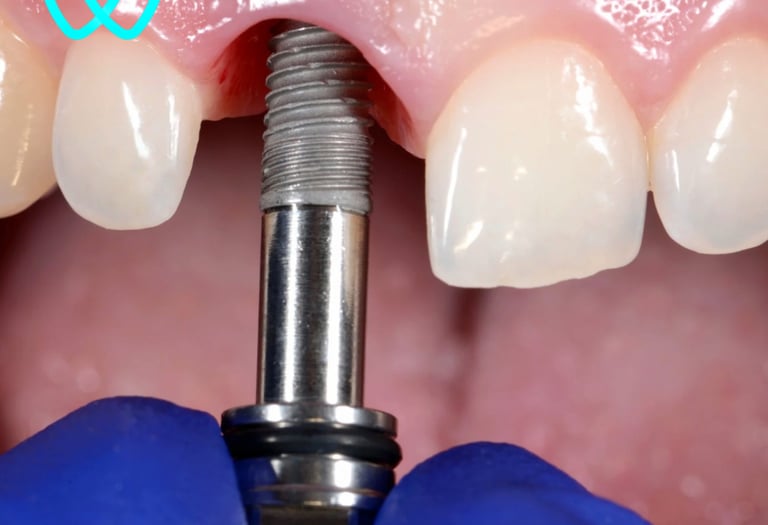

Los implantes dentales son la solución ideal para reemplazar dientes perdidos de forma permanente. Utilizamos materiales biocompatibles de alta calidad que se integran con el hueso, devolviendo la funcionalidad y la estética de tu sonrisa. Nuestro enfoque asegura resultados duraderos y naturales.

Implantes